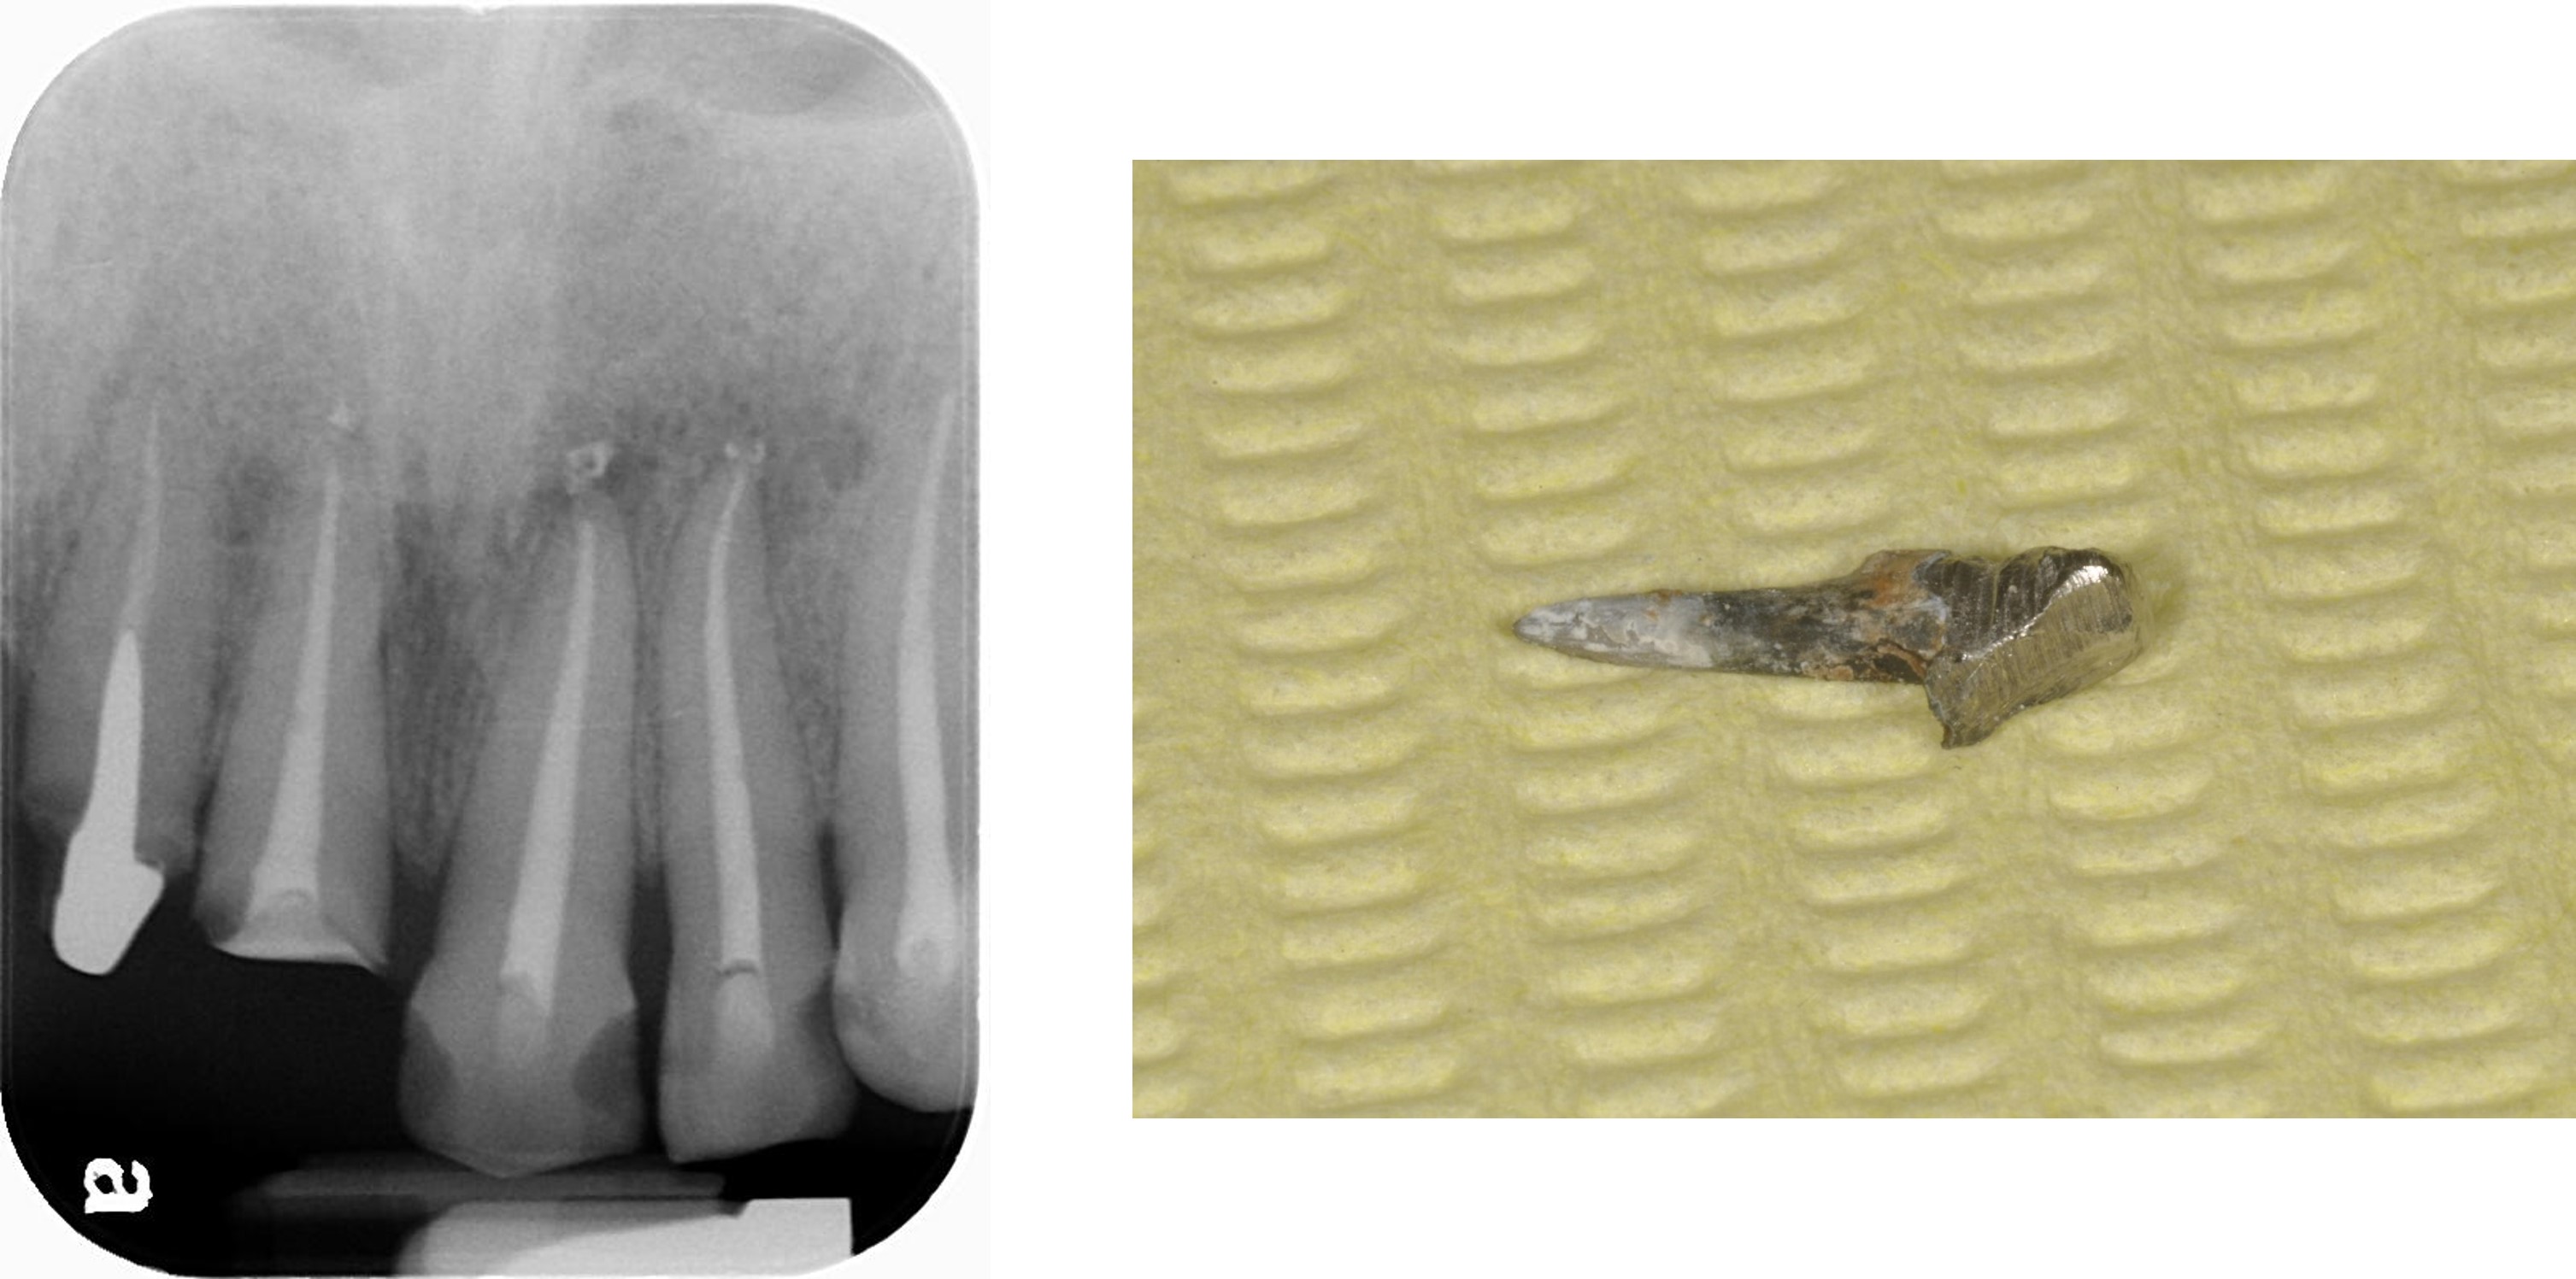

治療前,殘根與牙周支撐不良

上顎牙齒根管治療

移除舊釘柱